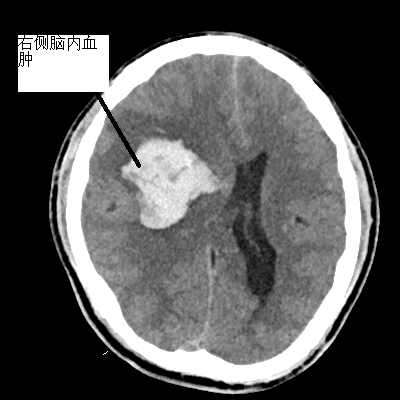

患者劉先生因勞作時突發(fā)左側(cè)肢體無力、言語不暢,伴有惡心、嘔吐胃內(nèi)容物數(shù)次,7月15日到我院急診科就診,初步診斷為右額顳頂葉-右基底節(jié)出血,出血量近50ml。家屬要求先予保守治療,患者入住我院神經(jīng)外科治療。之后患者意識障礙加深,呈模糊狀態(tài),對答部分回應(yīng),表現(xiàn)左側(cè)肢體無力,復(fù)查CT提示右額顳頂葉、基底節(jié)出血較前增加,出血量達(dá)60ml,周圍腦溝腦回、右側(cè)腦室受壓,中線向左部分偏移,環(huán)池部分受壓,有急診手術(shù)指征。

▲術(shù)前顱內(nèi)血腫